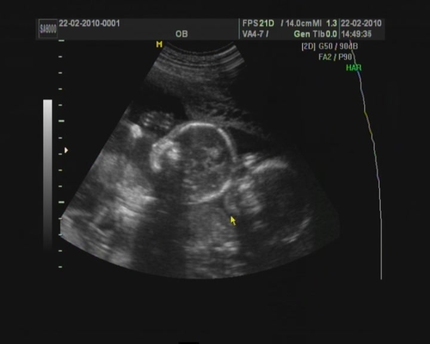

в мою секунду). О, и у вас, вероятно, было по крайней мере одно УЗИ в этот момент — которое ТАК взволновало (хотя иногда немного нервирует, если быть честным), и услышать сердцебиение вашего ребенка в первый раз — это одно из самые особенные звуки КОГДА-ЛИБО! Хорошо, на эти недели второго триместра —